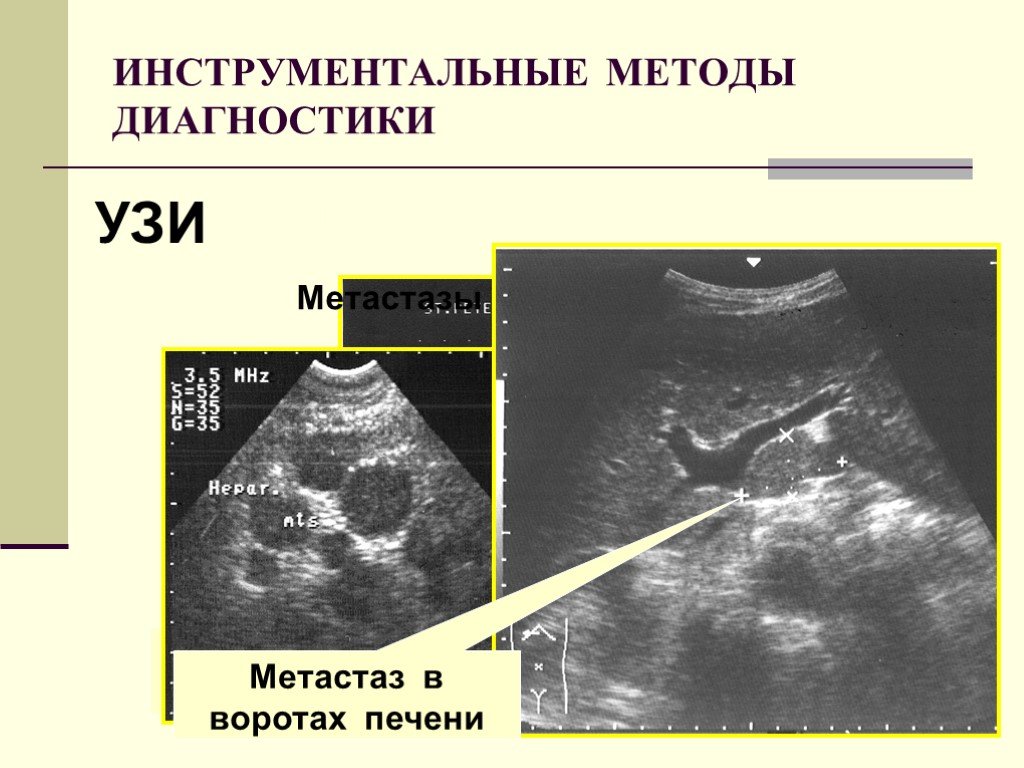

Метастатические поражения печени в ультразвуковом изображении характеризуются